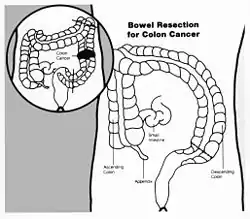

Drawing showing bowel resection for colon cancer | |

A bowel resection or enterectomy (enter- + -ectomy) is a surgical procedure in which a part of an intestine (bowel) is removed, from either the small intestine or large intestine. Often the word enterectomy is reserved for the sense of small bowel resection, in distinction from colectomy, which covers the sense of large bowel resection. Bowel resection may be performed to treat gastrointestinal cancer, bowel ischemia, necrosis, or obstruction due to scar tissue, volvulus, and hernias. Some patients require ileostomy or colostomy after this procedure as alternative means of excretion.[1] Complications of the procedure may include anastomotic leak or dehiscence, hernias, or adhesions causing partial or complete bowel obstruction. Depending on which part and how much of the intestines are removed, there may be digestive and metabolic challenges afterward, such as short bowel syndrome.

Cancer

Small bowel or colon cancer may require surgical resection.[7]

Colon cancer is the third most common cancer and the second most common cause of cancer death in the USA.[8] Due to its prevalence, screening protocols have been created for prevention of disease. Screening colonoscopies with or without polypectomy have been shown to decrease cancer morbidity and mortality.[9] When cancer is more advanced and polypectomy is not possible surgical resection is necessary. Using imaging and pathologic evaluation of resected tissue the tumor may be staged using AJCC stages.[9] Surgical resection of tumors for staging and for curative purposes requires removal of local blood vessel and lymph nodes. Standard lymph node resection includes three consecutive levels of lymph nodes and is known as a D3 lymphadenectomy.[10] In addition to surgery adjuvant chemotherapy may be used to decrease risk of recurrence. Chemotherapy is standard with stage III cancer, case dependant in stage II and palliative in stage IV.[11] Diet high in processed food and sugary drinks has also been shown to increase recurrence of stage III colon cancer.[12]